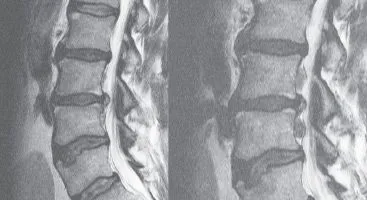

Multiple Severe Disc Herniations & Degeneration Lumbar Spine

Over the course of seven years, Bruce developed lower back pain that increasingly radiated down his left leg into his foot and eventually became disabling.